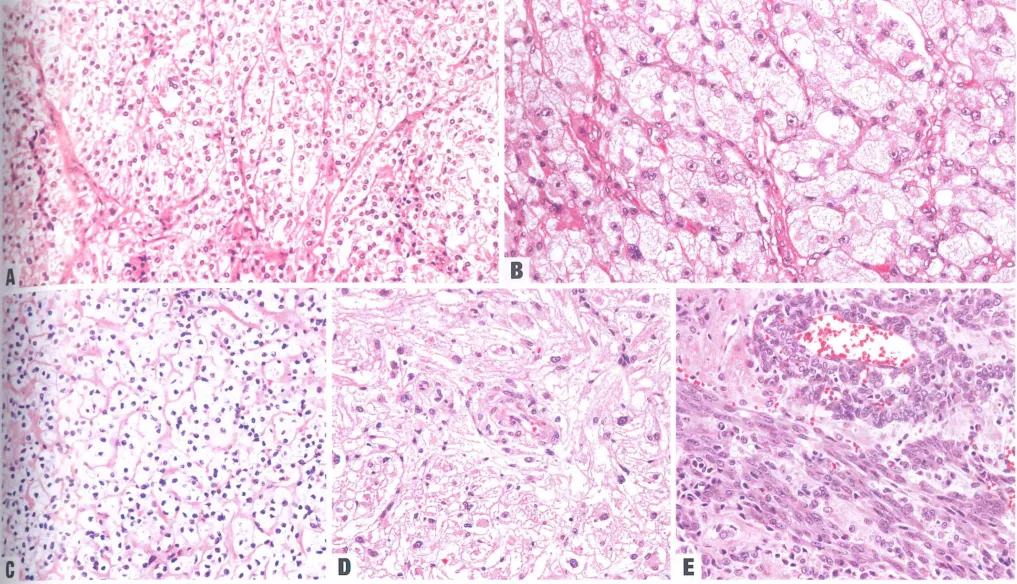

A 注意其典型的层状结构。B 上皮样肿瘤细胞含有大量透明的细胞质。C 该肿瘤由小簇状的透明细胞组成,细胞核呈小而圆状,细胞边界清晰(糖瘤)。D 一种呈片状生长模式的肿瘤。注意其颗粒状至透明状的细胞质以及细胞核的均匀形态。E 有些肿瘤呈现梭形细胞形态。